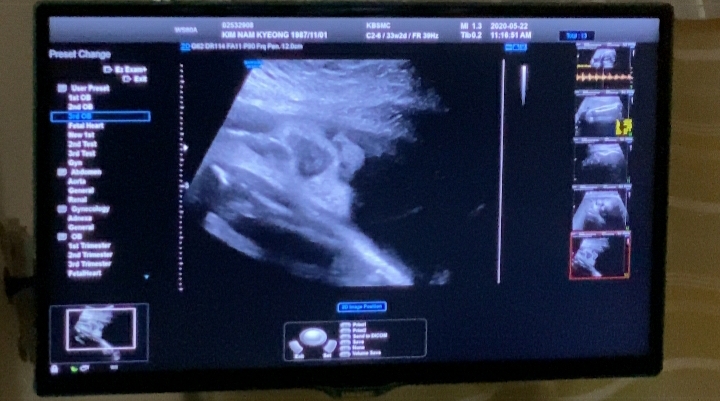

33주 정기검진 (소변검사)

30주가 넘으니 2주 마다 정기검진을 다니는데요 33주에는 소변검사만 하고 진료를 봤어요. 으아 근데 충격...